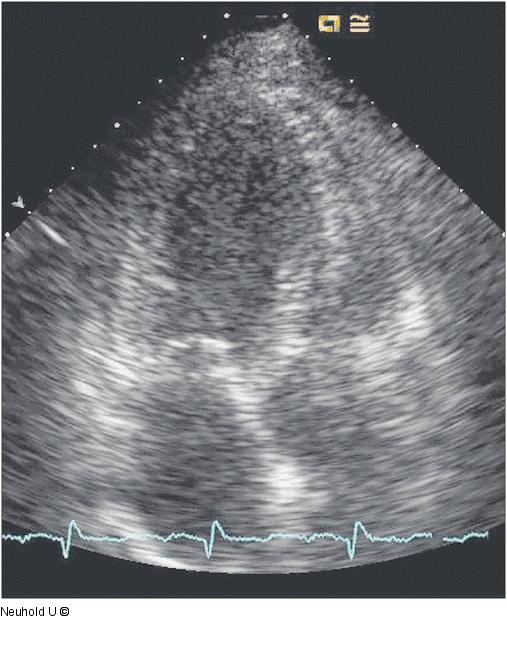

Abbildung 4: Dreikammerblick |